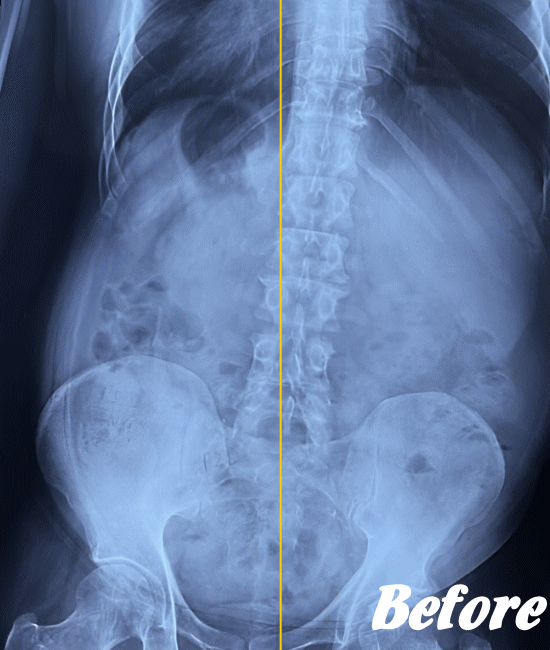

| 施術前(レントゲン) | 施術後(レントゲン) |

|---|---|